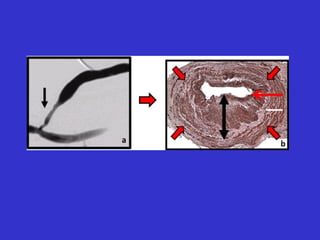

The Problem

The rapid, progressive development

of intimal hyperplasia at the anastomosis

of hemodialysis fistulae and grafts.

anastomotic

stenosis

PTFE graft anastomotic

AV fistula

Hemodialysis Graft Stenosis

at the

venous

anastomosis